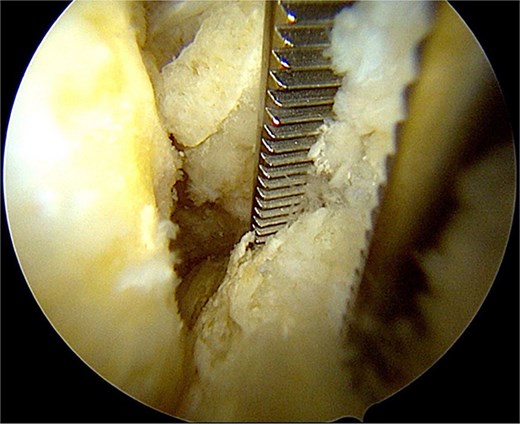

After partial resection of the infrapatellar fat pad for better visualization, the ossicle was exposed by finding the spinal needle and working around it. The fragment was freed arthroscopically using a motorized shaver and a radiofrequency probe (Fig. 5), taking care to protect the patellar tendon.

Once the ossicle was mobile and free (Fig. 6), it was removed either in one piece or was broken into multiple pieces with an arthroscopic burr and then removed with a grasper (Figs 7 and 8). Finally, the tibial tubercle was leveled using either an arthroscopic burr or shaver.

Arthroscopic views of case 1. (A) Ossicle fragment removed. Case 2 (B) tibial tubercle leveling using an arthroscopic Burr. Case 3 (C) ossicle fragment removed.